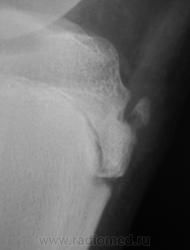

Пациент направлен на рентгенографию коленного сустава с диагнозом - Болезнь Осгут - Шлаттера.

фрагментация бугристости Б\Б кости

Болезнь Осгут - Шлаттера, как-то не вдохновляет. Более склонен к консоидирующемуся отрывному перелому бугристости б/берцовой кости.

Уважаемые коллеги! На мой взгляд, выявленное на рентгенограмме, образование костной плотности, с четкими, ровными контурами, однородное по своей структуре отношения с бугристости большеберцовой кости не имеет. Хотелось бы знать возраст пациента, его анамнез (спорт, травмы области коленного сустава). Больше похоже на обызвествления собственной связки надколенника. Дополнил бы УЗИ коленного сустава.

16 лет "учтенному лицу", ранее жалоб не было, рядом "мама", которой доктора посоветовали..., вот и вся история...